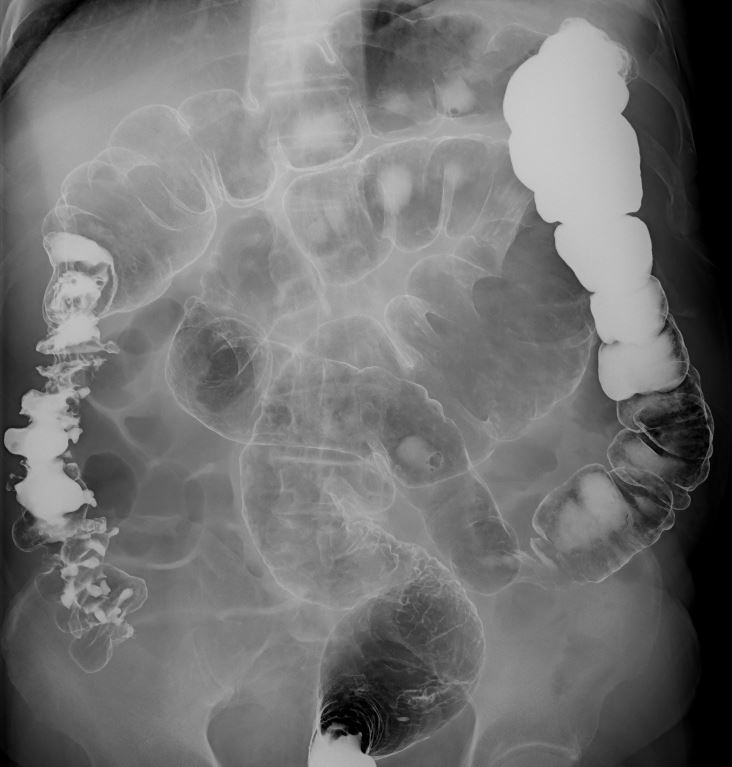

大腸造影検査は、造影剤を使って大腸の内部をX線で映し出し、ポリープや腫瘍、炎症などの異常を調べることができます。腸が重なり病変がわかりにくい場合は複数の角度からX線撮影し、それらの画像をコンピューターで立体的に再構成する断層撮影を行います。これにより、通常の撮影では見えにくい腸の重なりを分離して、より詳細で正確な画像が得られます。

大腸造影 |

大腸の断層画像 |